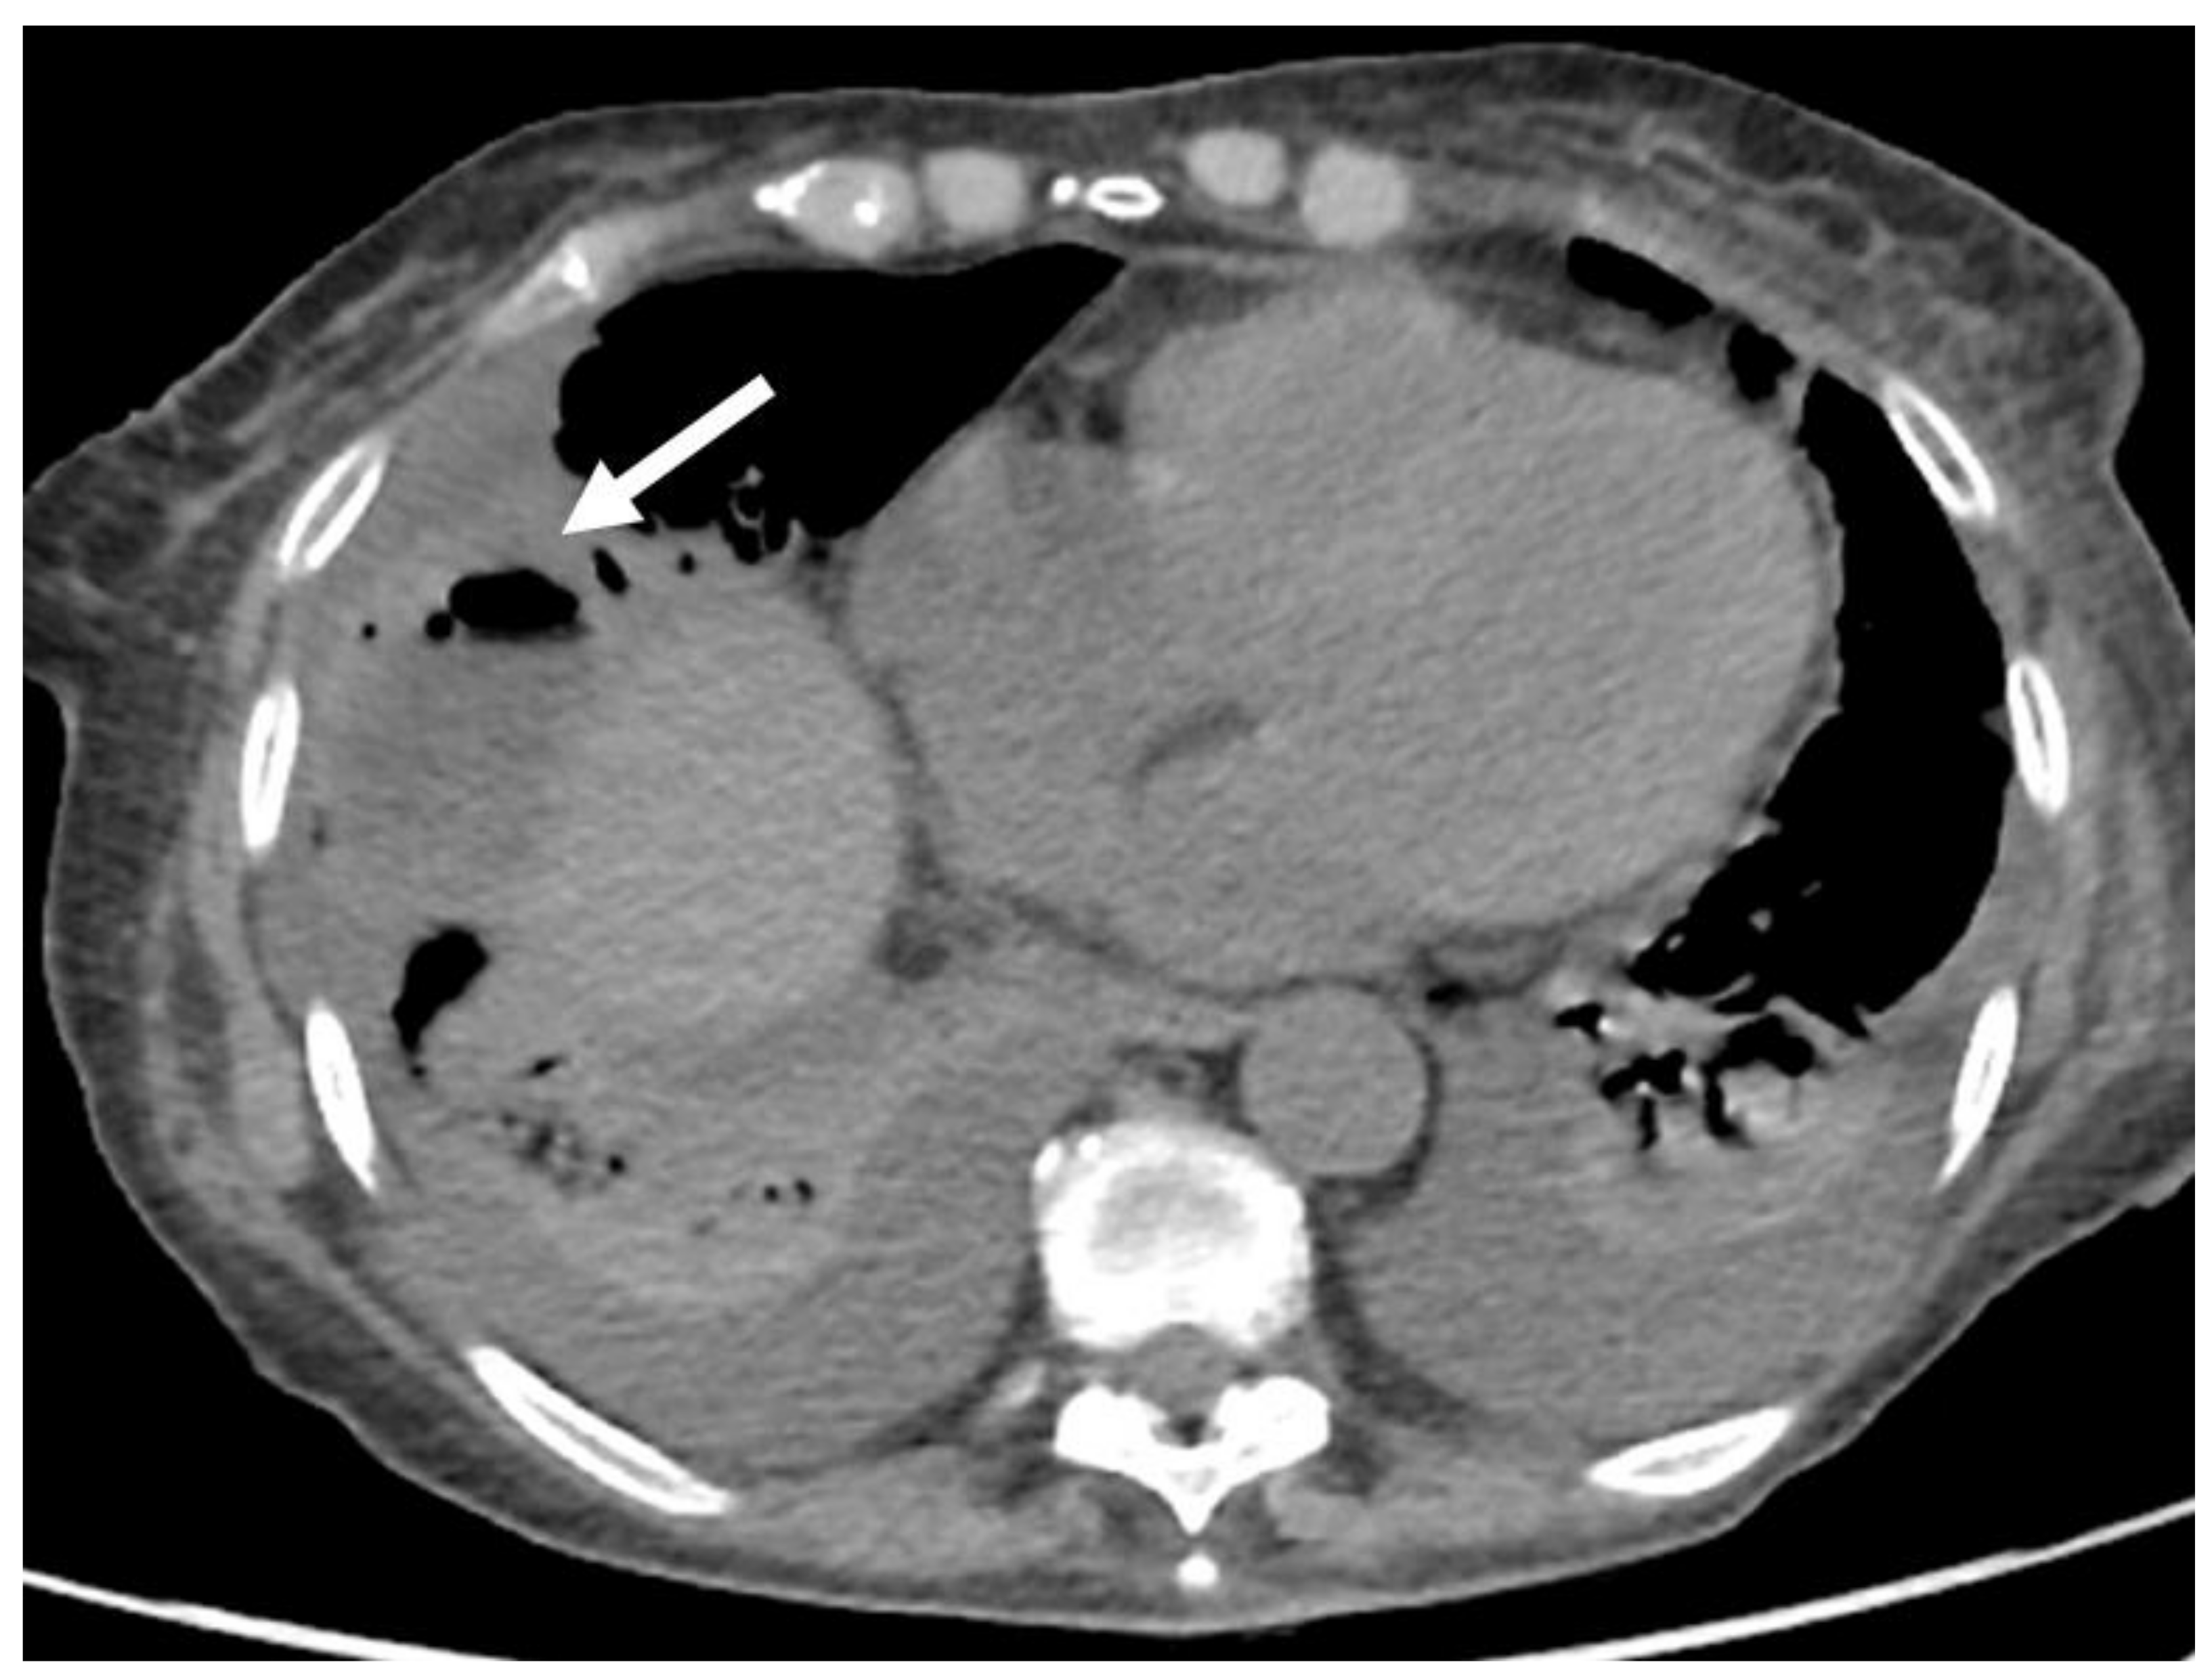

- Granata, V.; Grassi, R.; Fusco, R.; Belli, A.; Cutolo, C.; Pradella, S.; Grazzini, G.; La Porta, M.; Brunese, M.C.; De Muzio, F.; et al. Diagnostic evaluation and ablation treatments assessment in hepatocellular carcinoma. Infect. Agents Cancer 2021, 16, 53. [Google Scholar] [CrossRef] [PubMed]

- Izzo, F.; Granata, V.; Grassi, R.; Fusco, R.; Palaia, R.; Delrio, P.; Carrafiello, G.; Azoulay, D.; Petrillo, A.; Curley, S.A. Radiofrequency Ablation and Microwave Ablation in Liver Tumors: An Update. Oncologist 2019, 24, e990–e1005. [Google Scholar] [CrossRef] [Green Version]

- Granata, V.; Grassi, R.; Fusco, R.; Setola, S.V.; Palaia, R.; Belli, A.; Miele, V.; Brunese, L.; Petrillo, A.; Izzo, F. Assessment of Ablation Therapy in Pancreatic Cancer: The Radiologist’s Challenge. Front. Oncol. 2020, 10, 560952. [Google Scholar] [CrossRef]

- Fang, C.; Cortis, K.; Yusuf, G.T.; Gregory, S.; Lewis, D.; Kane, P.; Peddu, P. Complications from percutaneous microwave ablation of liver tumours: A pictorial review. Br. J. Radiol. 2019, 92, 20180864. [Google Scholar] [CrossRef]